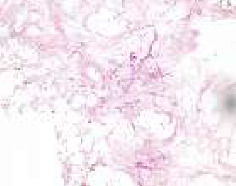

简介:毛霉病是一种罕见但严重的感染引起的真菌称为毛霉菌。它是一种危及生命的、高度侵袭性的血管侵入性感染,主要影响免疫功能低下的人群。方法和结果:2021年至2023年初,在塞尔维亚贝尔格莱德大学口腔医学院颌面外科诊所(“诊所”),医疗小组(“小组”)治疗了5名患有鼻-眶-脑型毛霉菌病的患者。在发现毛霉病之前,所有5名患者最近都已从COVID-19感染中康复。他们都在新冠肺炎专科医院度过了相当长的时间(平均住院1个月)。该小组根据2019冠状病毒病大流行时的毛霉病筛查诊断和管理指南(2019冠状病毒病患者指南/印度医学研究委员会,2021年5月出版,经世卫组织批准)对这些患者进行了治疗。治疗包括几个阶段,其中小组负责并开展早期诊断和手术干预阶段,而其他诊所的同事则协助进行毛霉病的其他治疗/管理阶段。结论:本文的目的是提出5例诊断为毛霉病的患者,特别关注两例因其病情接受手术干预作为抗真菌治疗的一部分的患者。

Introduction: Mucormycosis is a rare but serious infection caused by fungi called mucormycetes. It is life-threatening, highly aggressive angioinvasive infection, which mainly affects immunocompromised people. Methods and Results: During 2021-early 2023, at the Clinic for Maxillofacial Surgery, Faculty of Dental Medicine, University of Belgrade, Serbia (the "Clinic"), medical team (the "Team") treated five patients, with a rhino-orbital-cerebral form of mucormycosis. All five patients had recently recovered from COVID-19 infection prior to detection of mucormycosis. All of them spent a considerable amount of time (on average 1 month of hospitalization) at COVID-19 specialized hospitals. The Team treated these patients following the guidelines for screening diagnosis and management of mucormycosis at the time of the COVID-19 pandemic (COVID-19 patient guidelines/Indian Council of Medical Research, published in May 2021 approved by WHO). Treatment included several phases, out of which the Team was responsible for and carried out early diagnosis and surgical intervention phase, while colleagues from other clinics assisted in other phases of treatment/management of mucormycosis. Conclusion: The goal of this paper is to present five patients diagnosed with mucormycosis, with a special focus on two patients who, due to their condition, received surgical intervention as part of their antifungal treatment.